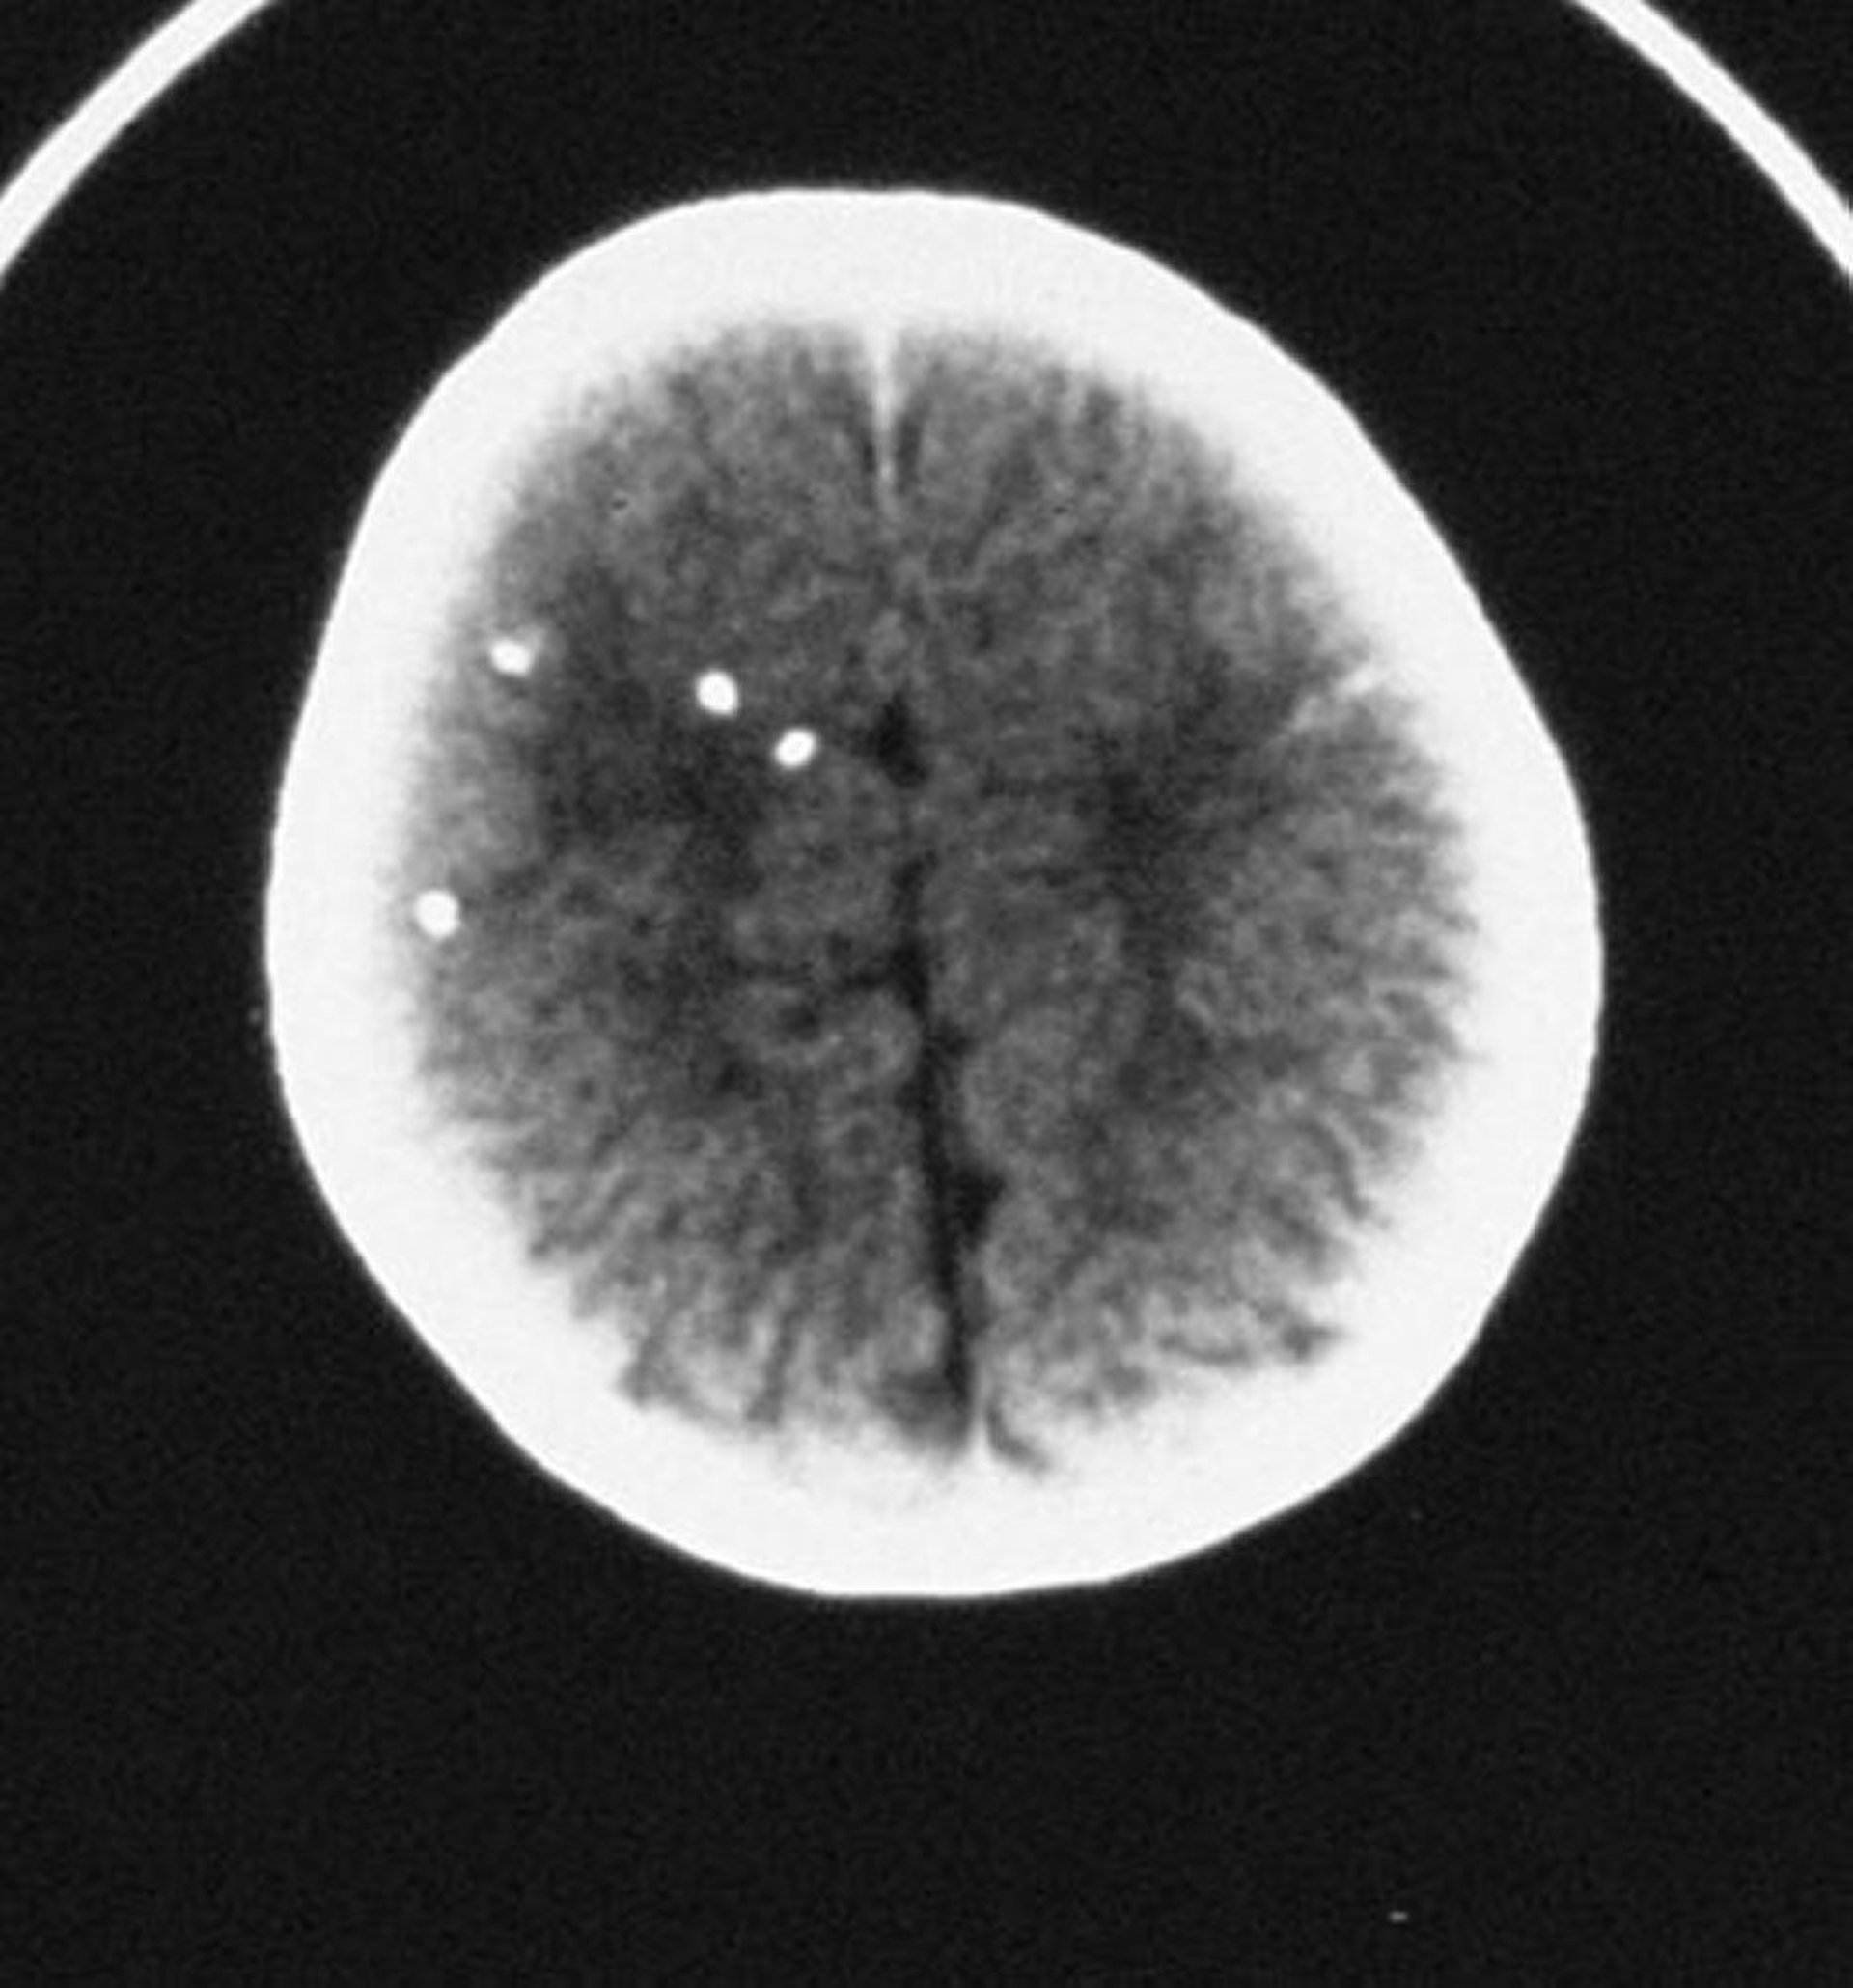

Toxoplasmosi congenita

Questa scansione TC mostra calcificazioni intracraniche diffuse.